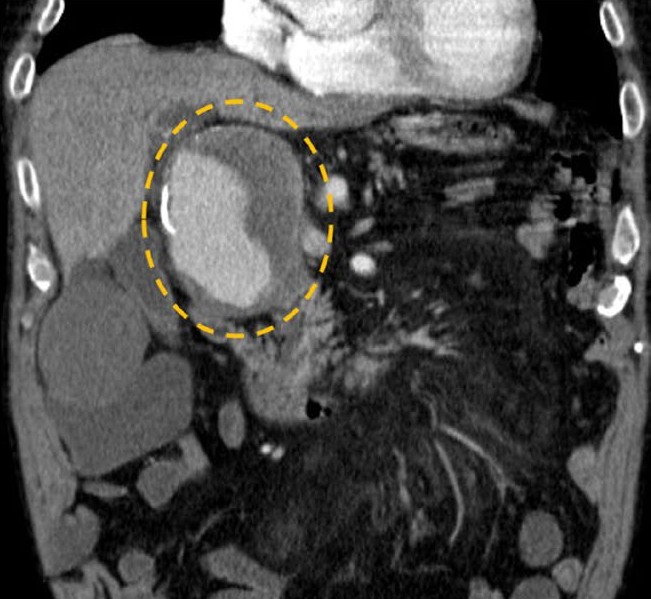

• An Uncommon Cause of Post-Hepatic Jaundice: Gastroduodenal Artery Aneurysm

Constantin Sitari, Rosario Blanco Sáez, Pedro Alves

109-110

DOI: https://doi.org/10.60591/crspmi.400